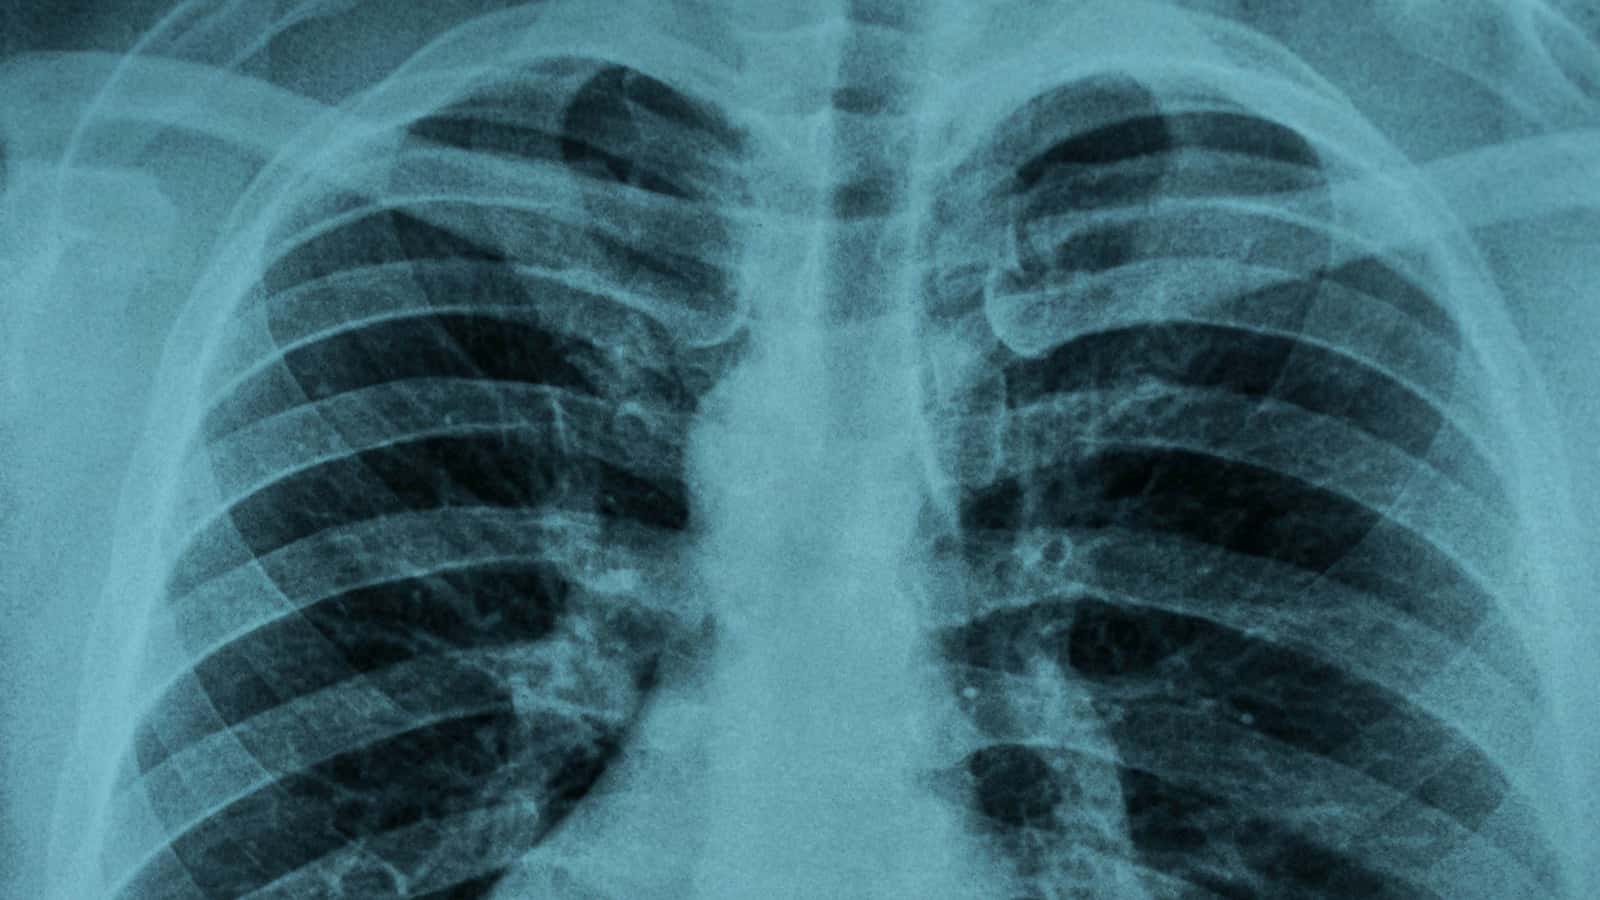

• Imaging can be helpful. A chest X-ray or CT scan can reveal how much inflammation exists inside the lungs.